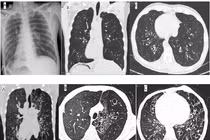

2 bệnh nhân mắc hội chứng Kartagener, đảo ngược phủ tạng hiếm gặp được phát hiện từ các triệu chứng viêm đường hô hấp tái diễn nhiều lần. Xét nghiệm gene hội chứng Kartagener thường khó thực hiện và tốn kém, chủ yếu dựa vào biểu hiện của tam chứng.